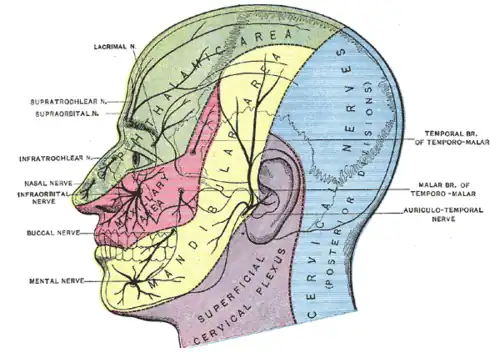

Dermatome distribution of the trigeminal nerve

Dermatome distribution of the trigeminal nerve -